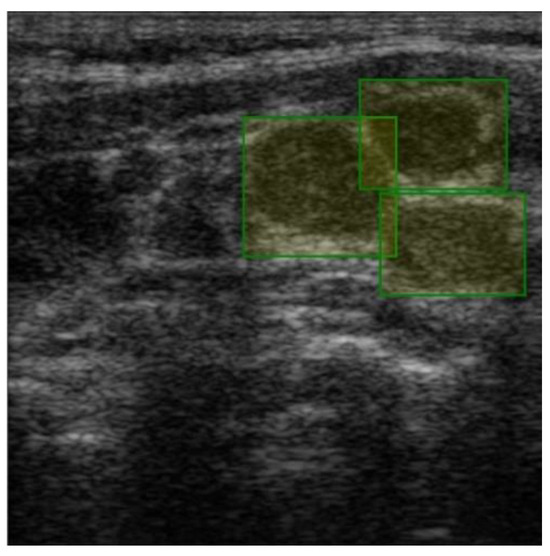

Labeling was conducted using a free online tool (ImgLab) (Figure 3). The labels were made by the team of physicians that selected the images. Overlapping labels were not a problem for our neural network because the lymph nodes were individually cropped. Therefore, the lymph node images within an adenopathic block were all labeled individually (Figure 4). The labels were saved in .json file format.

Figure 3. Manually created label over a single malignant adenopathy, generating X and Y coordinates for each corner of the box.

Jmms 12 00029 g003

Figure 4. Individual labels on each lymph node, generating X and Y coordinates for each corner of each box.

Jmms 12 00029 g004